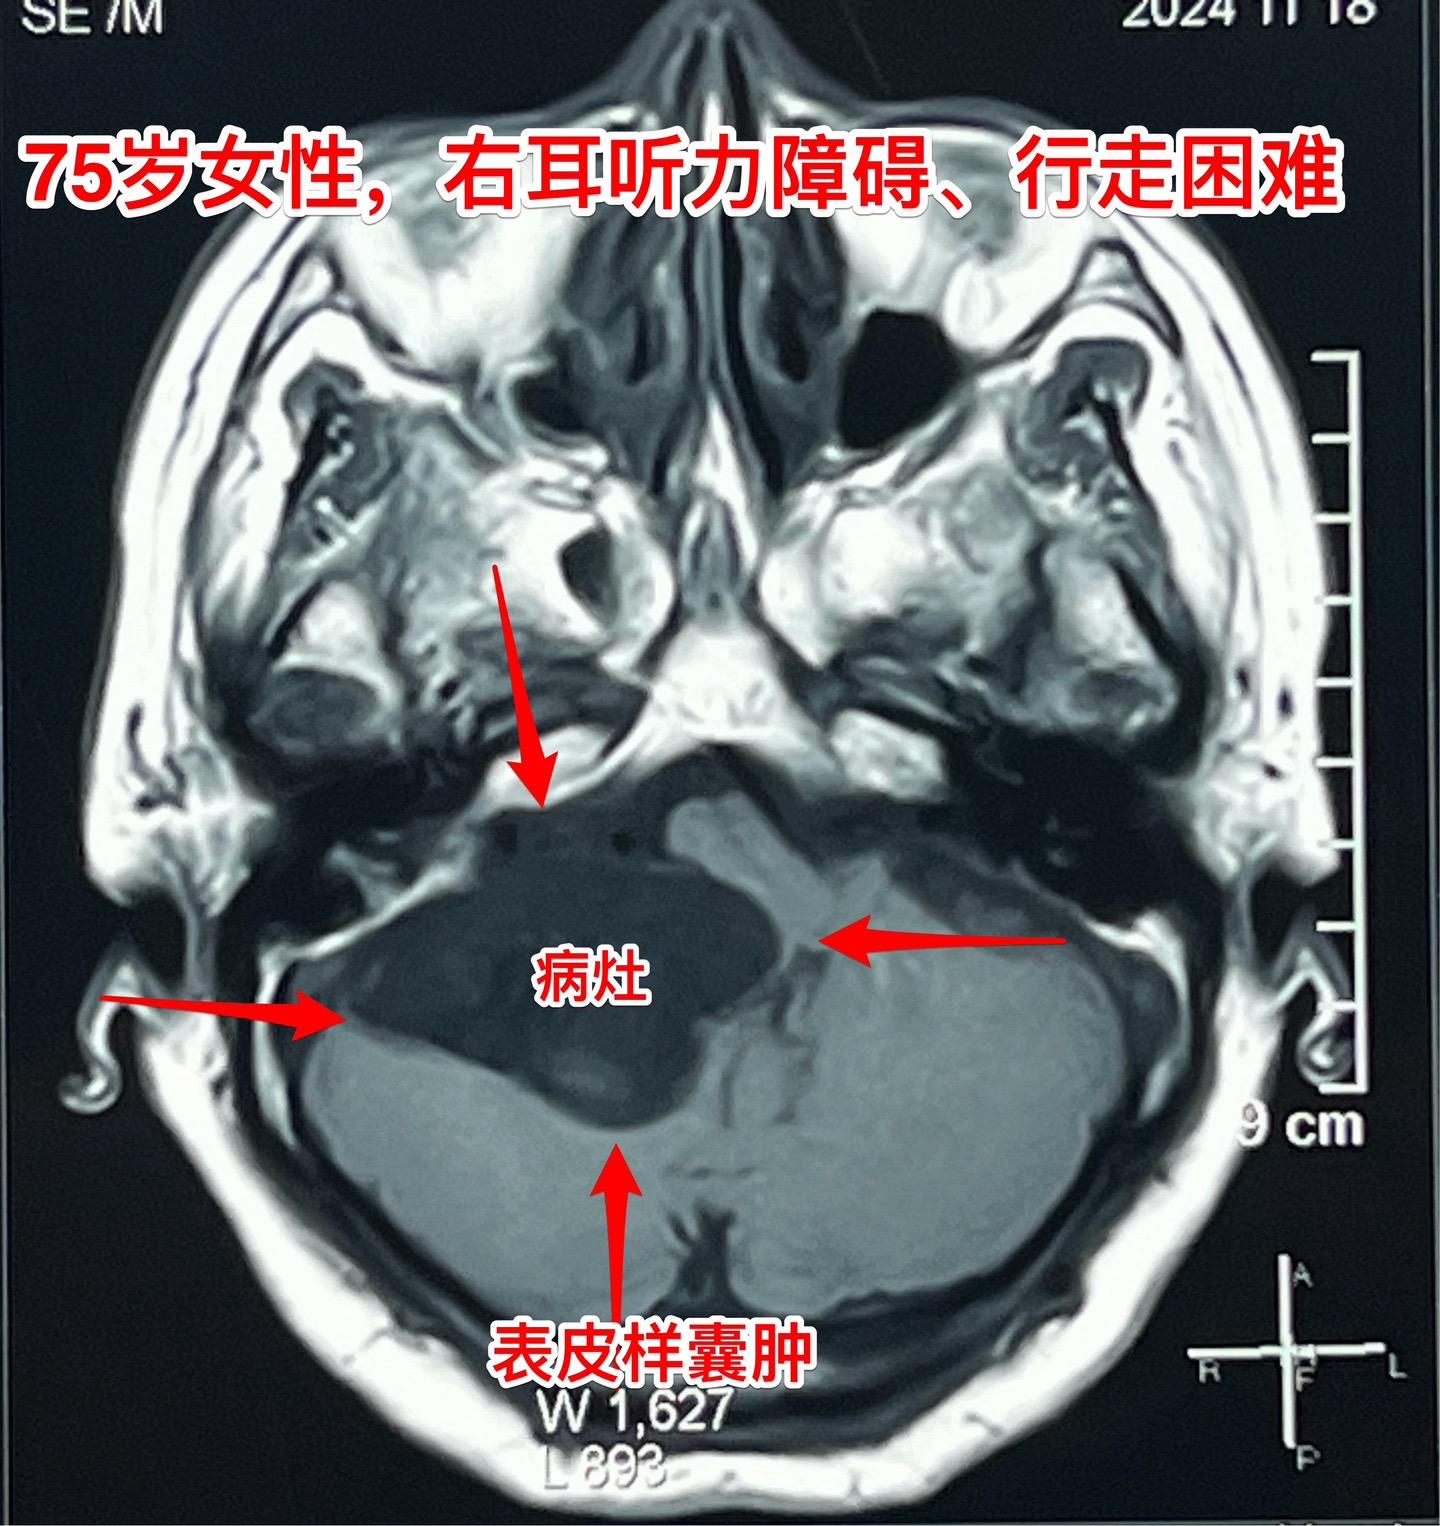

75岁的老奶奶决定接受开颅手术了!75岁的辽宁省海城老奶奶在5年前就曾发现脑部长了一个可疑肿瘤(怀疑为表皮样囊肿或者胆脂瘤),右耳听力下降。当时在沈阳就医,医生建议作手术,但是考虑到病人已经70岁高龄了,手术风险很大,当时老人和家属就决定不作手术。 在五年时间内老人的病情在慢慢加重,逐渐出现行走困难,生活质量越来越差。儿女孝顺,都想方设法地希望能够改善老人的生活质量! 老人的女婿有个表哥,张先生,患颅咽管瘤,曾经在2016年因颅咽管瘤复发了在我这里作了手术。手术后8年了,